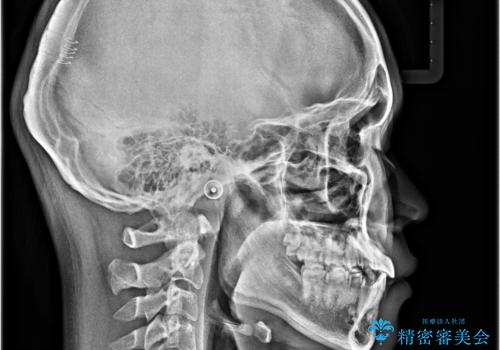

- 前歯のデコボコと口元の突出感を気にして来院された患者様です。

上下前歯がくちばしのように突出していたため、上下左右の第一小臼歯4本を抜歯し、ワイヤー装置にて矯正治療を行うこととしました。

左上は第二小臼歯が90度捻れており、状態が良くない歯であったため、左のみ第二小臼歯を抜歯することとしました。

第二小臼歯抜歯により治療期間が長くなることを了承いただき、治療を開始しました。

上顎骨に対して下顎骨がやや前方位に位置しているため、下顎前歯をあまり内側に移動させることができず、口元の突出感改善は期待以上にはならないと予測しておりましたが、満足いくの引っ込み具合となりました。